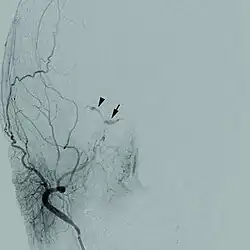

| Cerebral angiogram of a carotid-cavernous fistula | |